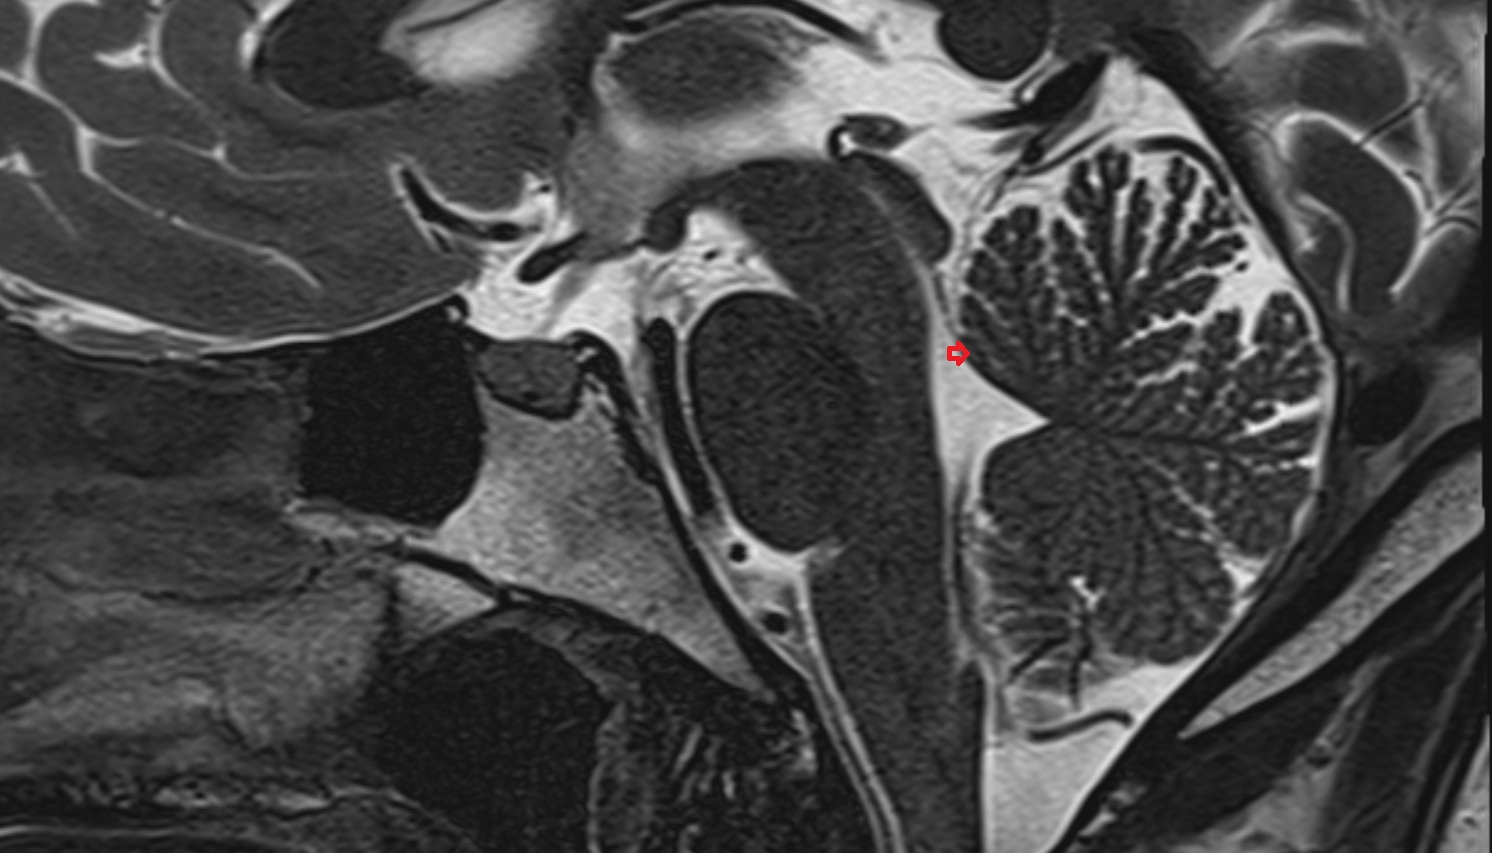

- Arbor Vitae (Cerebellar White Matter)

- Cerebellum

- Lingula of cerebellum (I)

- Central lobule (II & III) of Cerebellum

- Culmen (IV, V) of Cerebellum

- Declive (VI) of Cerebellum

- Folium (VII) of Cerebellum

- Tuber of vermis (VII)

- Pyramid of vermis (VIII)

- Uvula of vermis (IX)

- Nodule of vermis (X)

- Cerebellar tonsil (H IX)